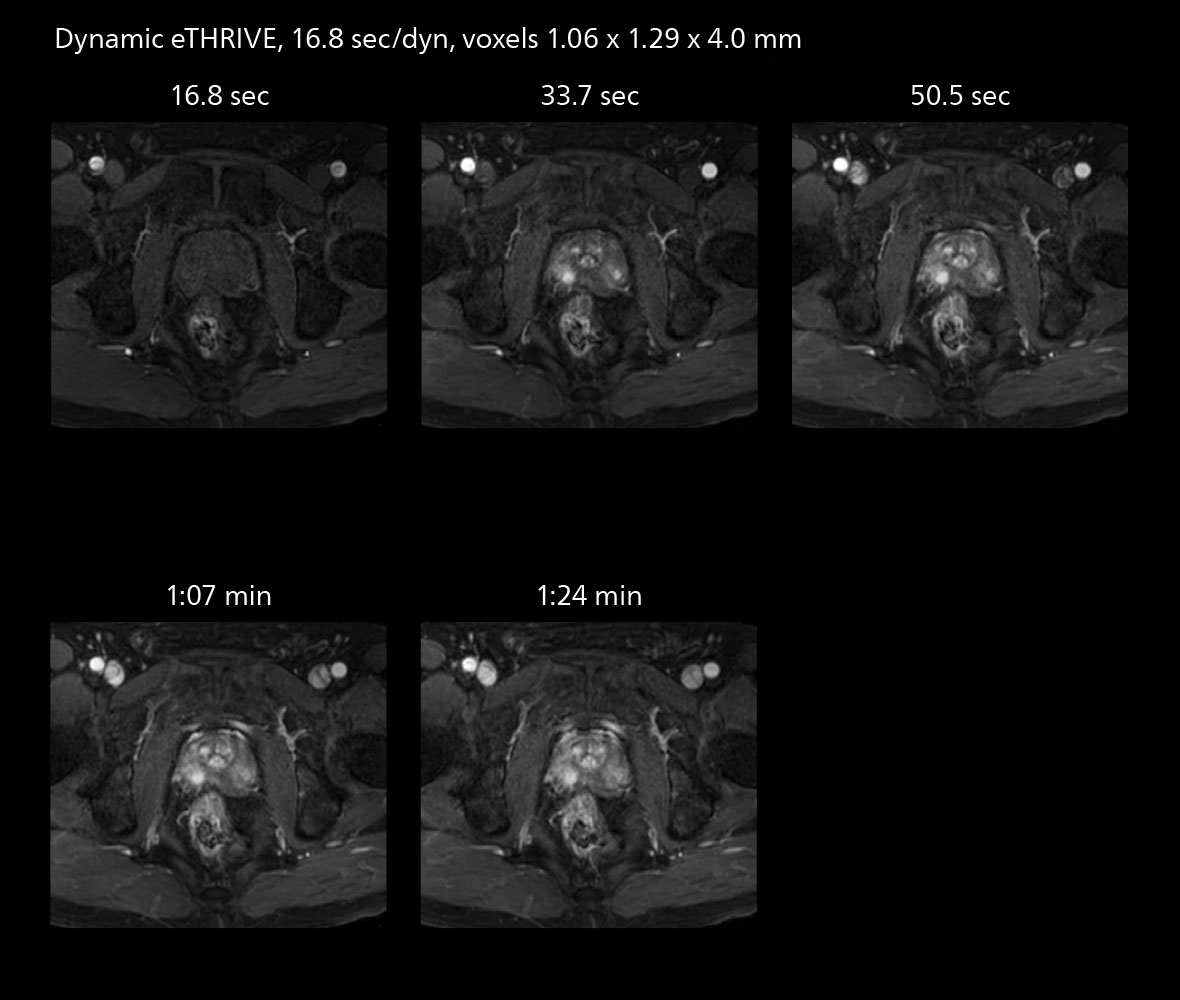

The value of the Elition X gradients is also evident in DWIBS studies. “The fact that we can consistently obtain distortion‐free DWIBS while reducing imaging time at three coronal stations is excellent,” Dr. Makuuchi says. “In these patients, it’s also important that the application of Compressed SENSE to T2‐weighted, STIR and mDIXON sequences has no impact on the examination time of whole‐body imaging. As a result of the increased speed and higher image quality we realize, DWIBS studies have now become routine examinations.”

With SmartPath to Elition X the team can obtain excellent quality DWIBS imaging and reduce imaging time. Other sequences also fit in the examination slot. This case shows left paravertebral neurogenic tumor and Th10 vertebral hemangiomas.